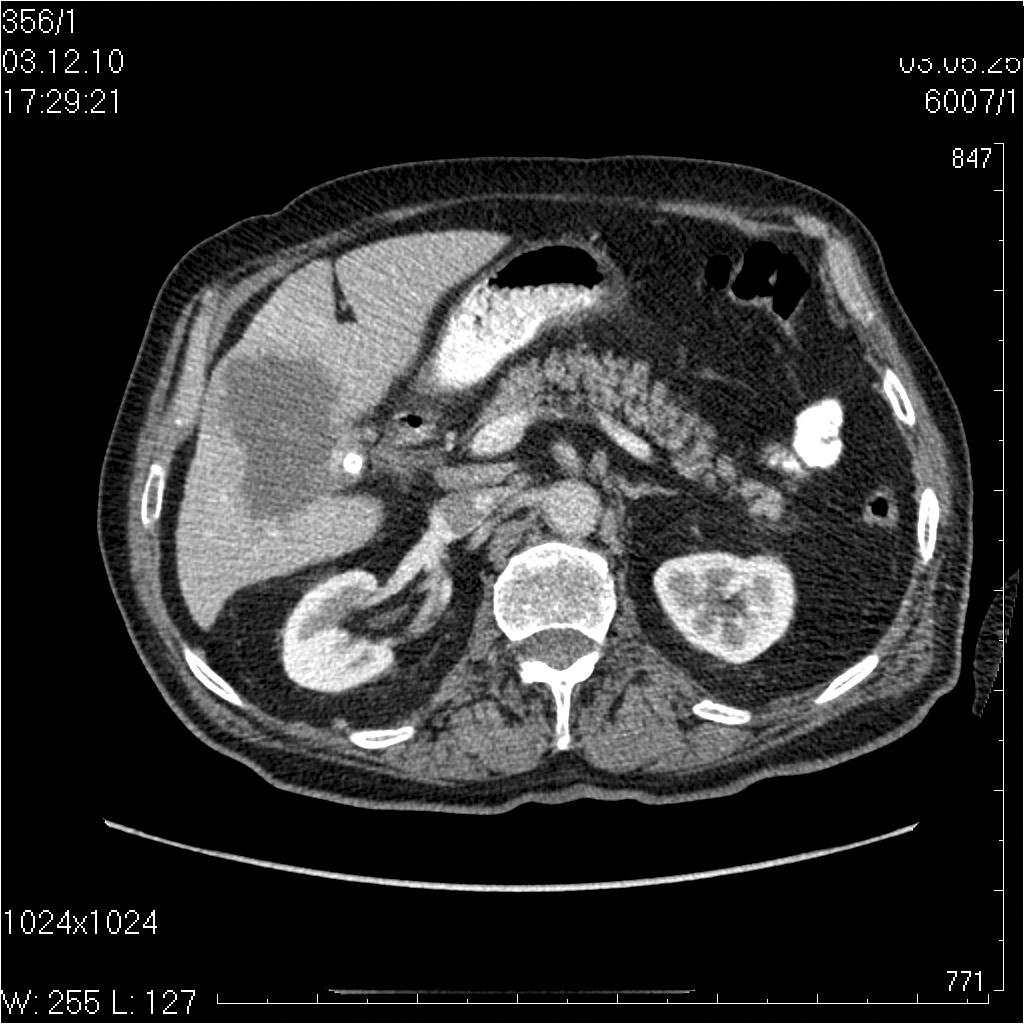

Пожилой мужчина с невыраженными болями в правом подреберье.

видео КТ

Диагностическая лапаротомия - Рак желчноо пузыря с прорастанием в паренхиму печени

tags: gallbladder, adenocarcinoma, cancer, ultrasonography, CT